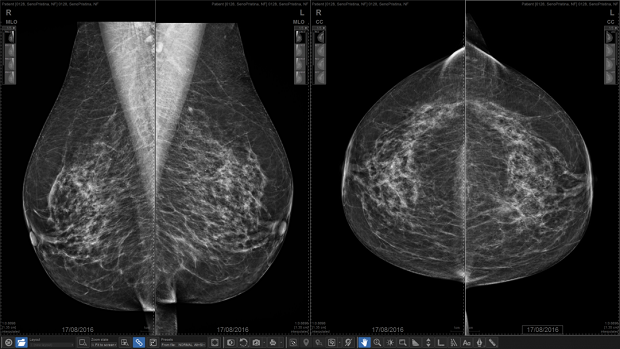

Mamografi hakkında 10 soru 10 cevap

Mamografi X-ışını kullanılan bir yöntemdir. Alınan radyasyonun bir kanseri tetikleme ihtimali teorik olarak çok düşüktür. Günümüzde yeni teknoloji dijital mamografi cihazlarıyla, tetkik sırasında alınan radyasyon miktarı çok azalmıştır. Mamografi sırasında alınan radyasyon miktarı bir uçak yolculuğu sırasında güneş ışınları nedeniyle maruz kaldığımız radyasyon ile hemen hemen aynıdır. Uçak yolculuklarından vazgeçiyor muyuz?

40 yaşından itibaren tarama amaçlı rutin olarak her yıl mamografi tetkiki yapılmalıdır. Yoğun içerikli meme dokularında, mamografik hassasiyet azalan olgularda ve mamografide bulgu saptanan olgularda, mamografiyi tamamlayıcı olarak ultrasonografi yapılmalıdır. 50 yaş üzeri kadınlarda da herhangi bir yaşta olabileceği gibi, ultrasonografi rahatlıkla yapılabilir.

Mamografi tetkiki 40 yaşından itibaren yılda bir defa düzenli olarak yaptırılmalıdır. Risk grubunda olan kadınlara tetkikler daha erken yaşta da önerilebilir. Bu konuyu hekiminize danışmanızda yarar var.